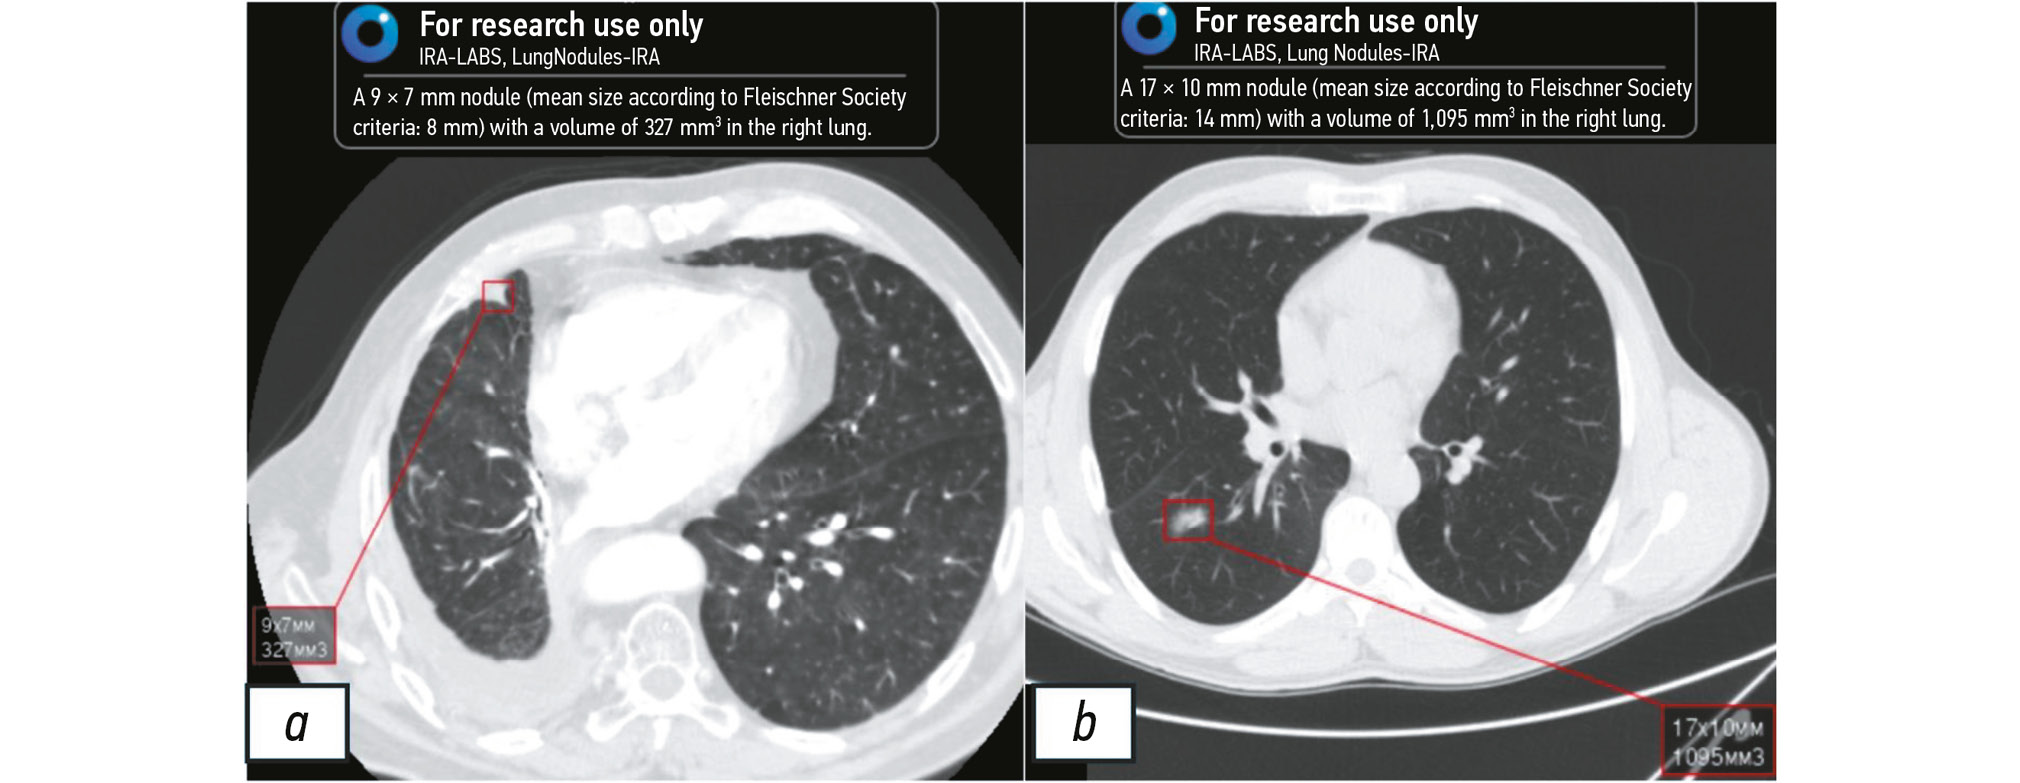

Fig. 3 and Fig. 4 illustrate the AI algorithm findings.

Fig. 3. Left lung nodule detected by artificial intelligence. The detected nodule is marked by the red square. Image with a high probability of lung cancer.

Fig. 4. Nodules in the right (a) and left (b) lungs detected by artificial intelligence. The detected nodules are marked by the red square. Images with inconclusive signs of lung cancer.